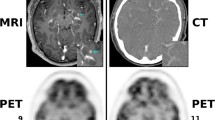

All patients underwent an FDG-PET study either using a stand-alone PET system or a PET-CT scanner under standard clinical protocol. Images were obtained 60–90 minutes after FDG administration. Images were reviewed by a nuclear physician and a surgical oncologist. Standard uptake values (SUV) of the target lesion(s) were measured. The PET probe-guided surgery decision was made after careful review of the imaging information and the clinical indications at a multidisciplinary conference.

In patients with lymphoma the PET probe was used to locate a non-palpable lymph node during a diagnostic lymphadenectomy. The PET probe successfully located the target lymph nodes (neck, axilla and groin) in all cases. Figures 1, 2, 3 show a case of head and neck cancer where PET probe was used for diagnostic lymphadenectomy in the neck. In patients who underwent a metastasectomy procedure, surgical exploration was clearly facilitated by the use of the probe. It helped lead to the successful accomplishment of the surgical end-point (resection of the image-detected lesion). Probe-guided exploration was most rewarding in secondary explorations where the lesion(s) were obscured by the scar tissue. Manipulation of the probe in the surgical field was easy without any access difficulties. PET probe-guided surgery protocol is detailed in Table 2.

FDG metabolism and clearance occurs at a much faster rate in normal tissues than tumor tissue, and thus TBR improves with time resulting in better lesion detection when imaging is delayed [17]. We have observed that tumor-to-non-tumor and tumor-to-organ rations were higher for the delayed images than for the 1.5-h routine images, and lesion detectability was improved in nodal and hepatic metastases. Our current study indicated that longer intervals accentuated the TBR, and resulted better lesion detection. The background radiation tends to decrease while the tumor uptake is retained. The in-situ TBR is also strongly affected by the areas of physiologic uptake or accumulation. The brain uptake in the head and neck region, cardiac uptake in the chest, kidney uptake and the accumulation inside the bladder in the abdomen and pelvis affect the in-situ TBR. Areas of physiologic uptake show attenuation over time, and use of an intraoperative bladder catheterization minimizes interference from bladder accumulation of FDG.